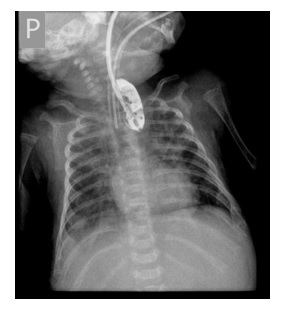

Zdjęcie prezentowane poniżej (wykonane u zaintubowanego noworodka, któremu wodny środek kontrastujący podawany jest przez cewnik do przełyku) jest diagnostyczne dla: